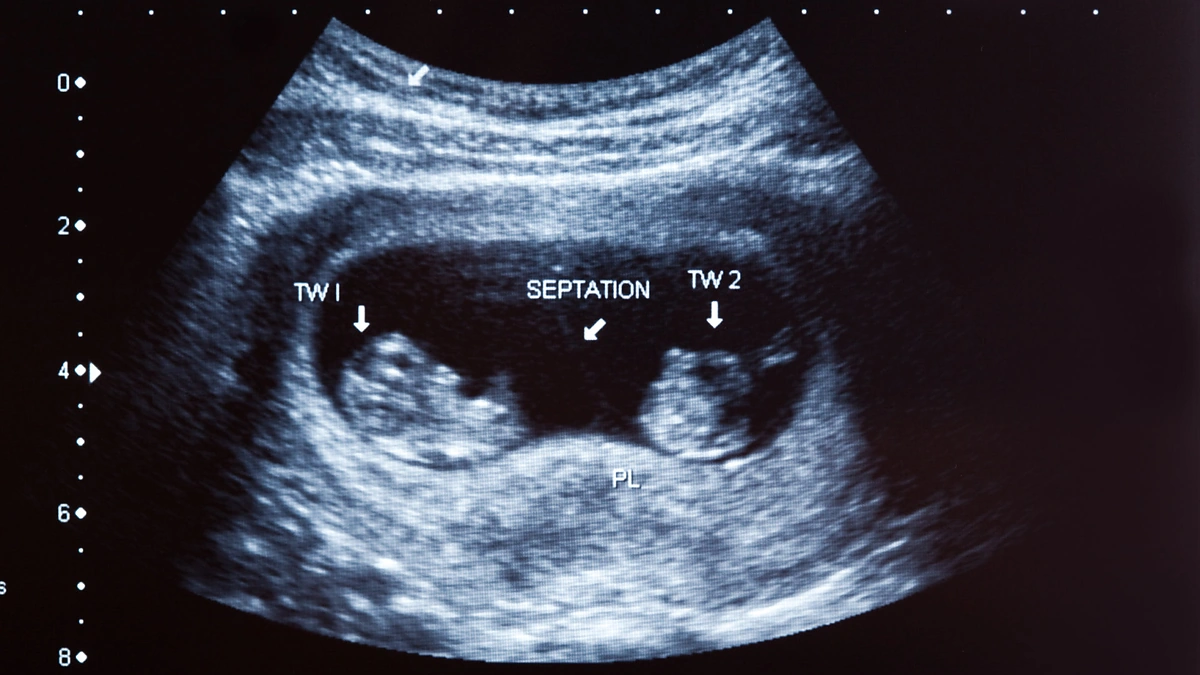

Lietuvoje dėl galiojančių įstatymų moterims atliekamas tik chirurginis nėštumo nutraukimas. Komplikacijos po aborto gali pasireikšti dėl įvairių priežasčių.

Vilniaus miesto klinikinės ligoninės akušeris ginekologas Tomas Lūža pasakoja, kad tam įtakos turi aborto atlikimo būdas, laikas ir pats moters organizmas. Sunku nustatyti, kaip jis gali sureaguoti į atliktą procedūrą. Kuo vėliau nutrauktas nėštumas, tuo didesnė komplikacijų rizika.